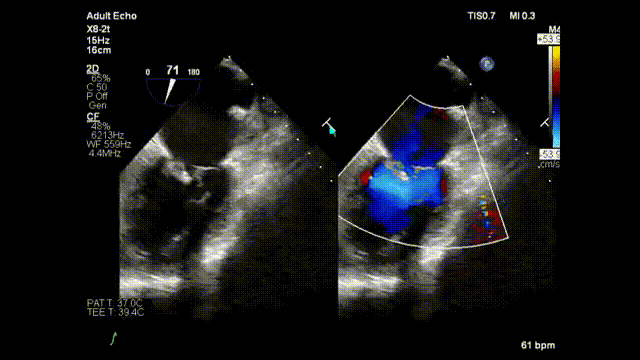

术毕二尖瓣反流减少为微量

手术正式开始,魏来教授和杨晔医生在心超诊断科董丽莉教授、赵维鹏教授的协助下,仅一个多小时就顺利完成了E-Chord™的穿刺“发射任务”。4根人工腱索被送入朱女士的心脏,准确锚定在二尖瓣脱垂病变区域。然后在超声引导下精确调整人工腱索长度并固定在心尖,从而恢复了朱女士正常的二尖瓣关闭功能。手术完成后朱女士二尖瓣反流立即由重度减少为微量;同时左房平均压明显改善,由术前42mmHg下降到24mmHg。手术全程在超声引导下进行,操作便捷可控,无放射线,心脏不停跳,无需体外循环,创伤小,不出血,恢复快。患者术后2小时即拔除气管插管并返回病房,第二天即可下床活动。